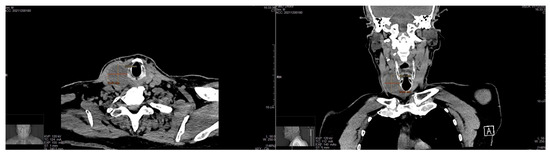

Background: Schwannomas, also called neurinomas, are rare benign tumors of the neural cells that can develop from the sheaths of nervous structures of several districts, although the most frequent sites are the cranial nerves (25%–45%). Rarely, cases show neck schwannomas in the thyroid parenchyma, while the cases of thyroid-bed schwannomas mimicking a thyroid-gland lesions are anecdotal. Methods: We report the case of a 70-year-old man with a preoperative-imaging diagnosis of a thyroid neoplasm, confirmed as Thyr 4 by fine-needle cytology. Results: During surgery, an extra-thyroidal lesion was discovered, determined to be a neck schwannoma through definitive pathology. A literature review of cases of thyroid-bed-lesion schwannomas misinterpreted as thyroid neoplasms was carried out. Conclusions: In the case of suspicious extra-thyroidal lesions, we advocate for a close routine cooperation between the cytologist, the radiologist, and the surgeon in the attempt to reach an accurate preoperative diagnosis. Full article

Figure 1